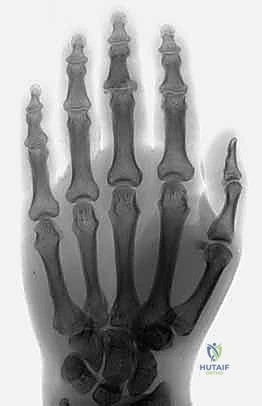

The cornerstone of diagnosis is plain radiology. Crucially, we need true posteroanterior (PA) and lateral radiographs centered specifically on the injured PIP joint. Hand radiographs alone, often taken in the emergency department, are inadequate.

Figures 5A-C emphasize that hand radiographs are only interpretable with a true lateral view of the PIP joint.

Fluoroscopy is invaluable for assessing injury dynamics and joint stability in real-time. It helps differentiate stable from unstable injuries, whether fracture-subluxations, dislocations, or pilon fractures. Subluxation and dislocation are best visualized on the lateral radiograph and can be subtle, appearing as joint incongruity or the "triangle sign" (dorsal overhang of the middle phalanx base).

Figure 4E illustrates dorsal fracture-subluxation with joint incongruity and the classic V-sign.

Diagnostic Imaging and Interpretation

As discussed, true PA and lateral radiographs of the PIP joint are non-negotiable. We meticulously assess the percentage of volar articular surface involvement, the degree of comminution, and any associated fractures. Fluoroscopy in the clinic can be invaluable for dynamic assessment of stability.